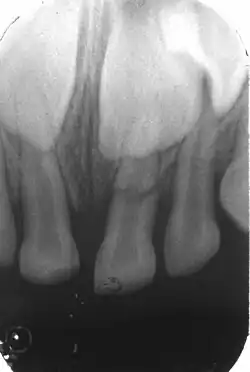

Kronenfraktur mit gut erkennbarer Pulpaeröffnung an Zahn 11. 16-jähriger Patient, -

Röntgenbild (Zahnfilm) des frakturierten Zahnes -